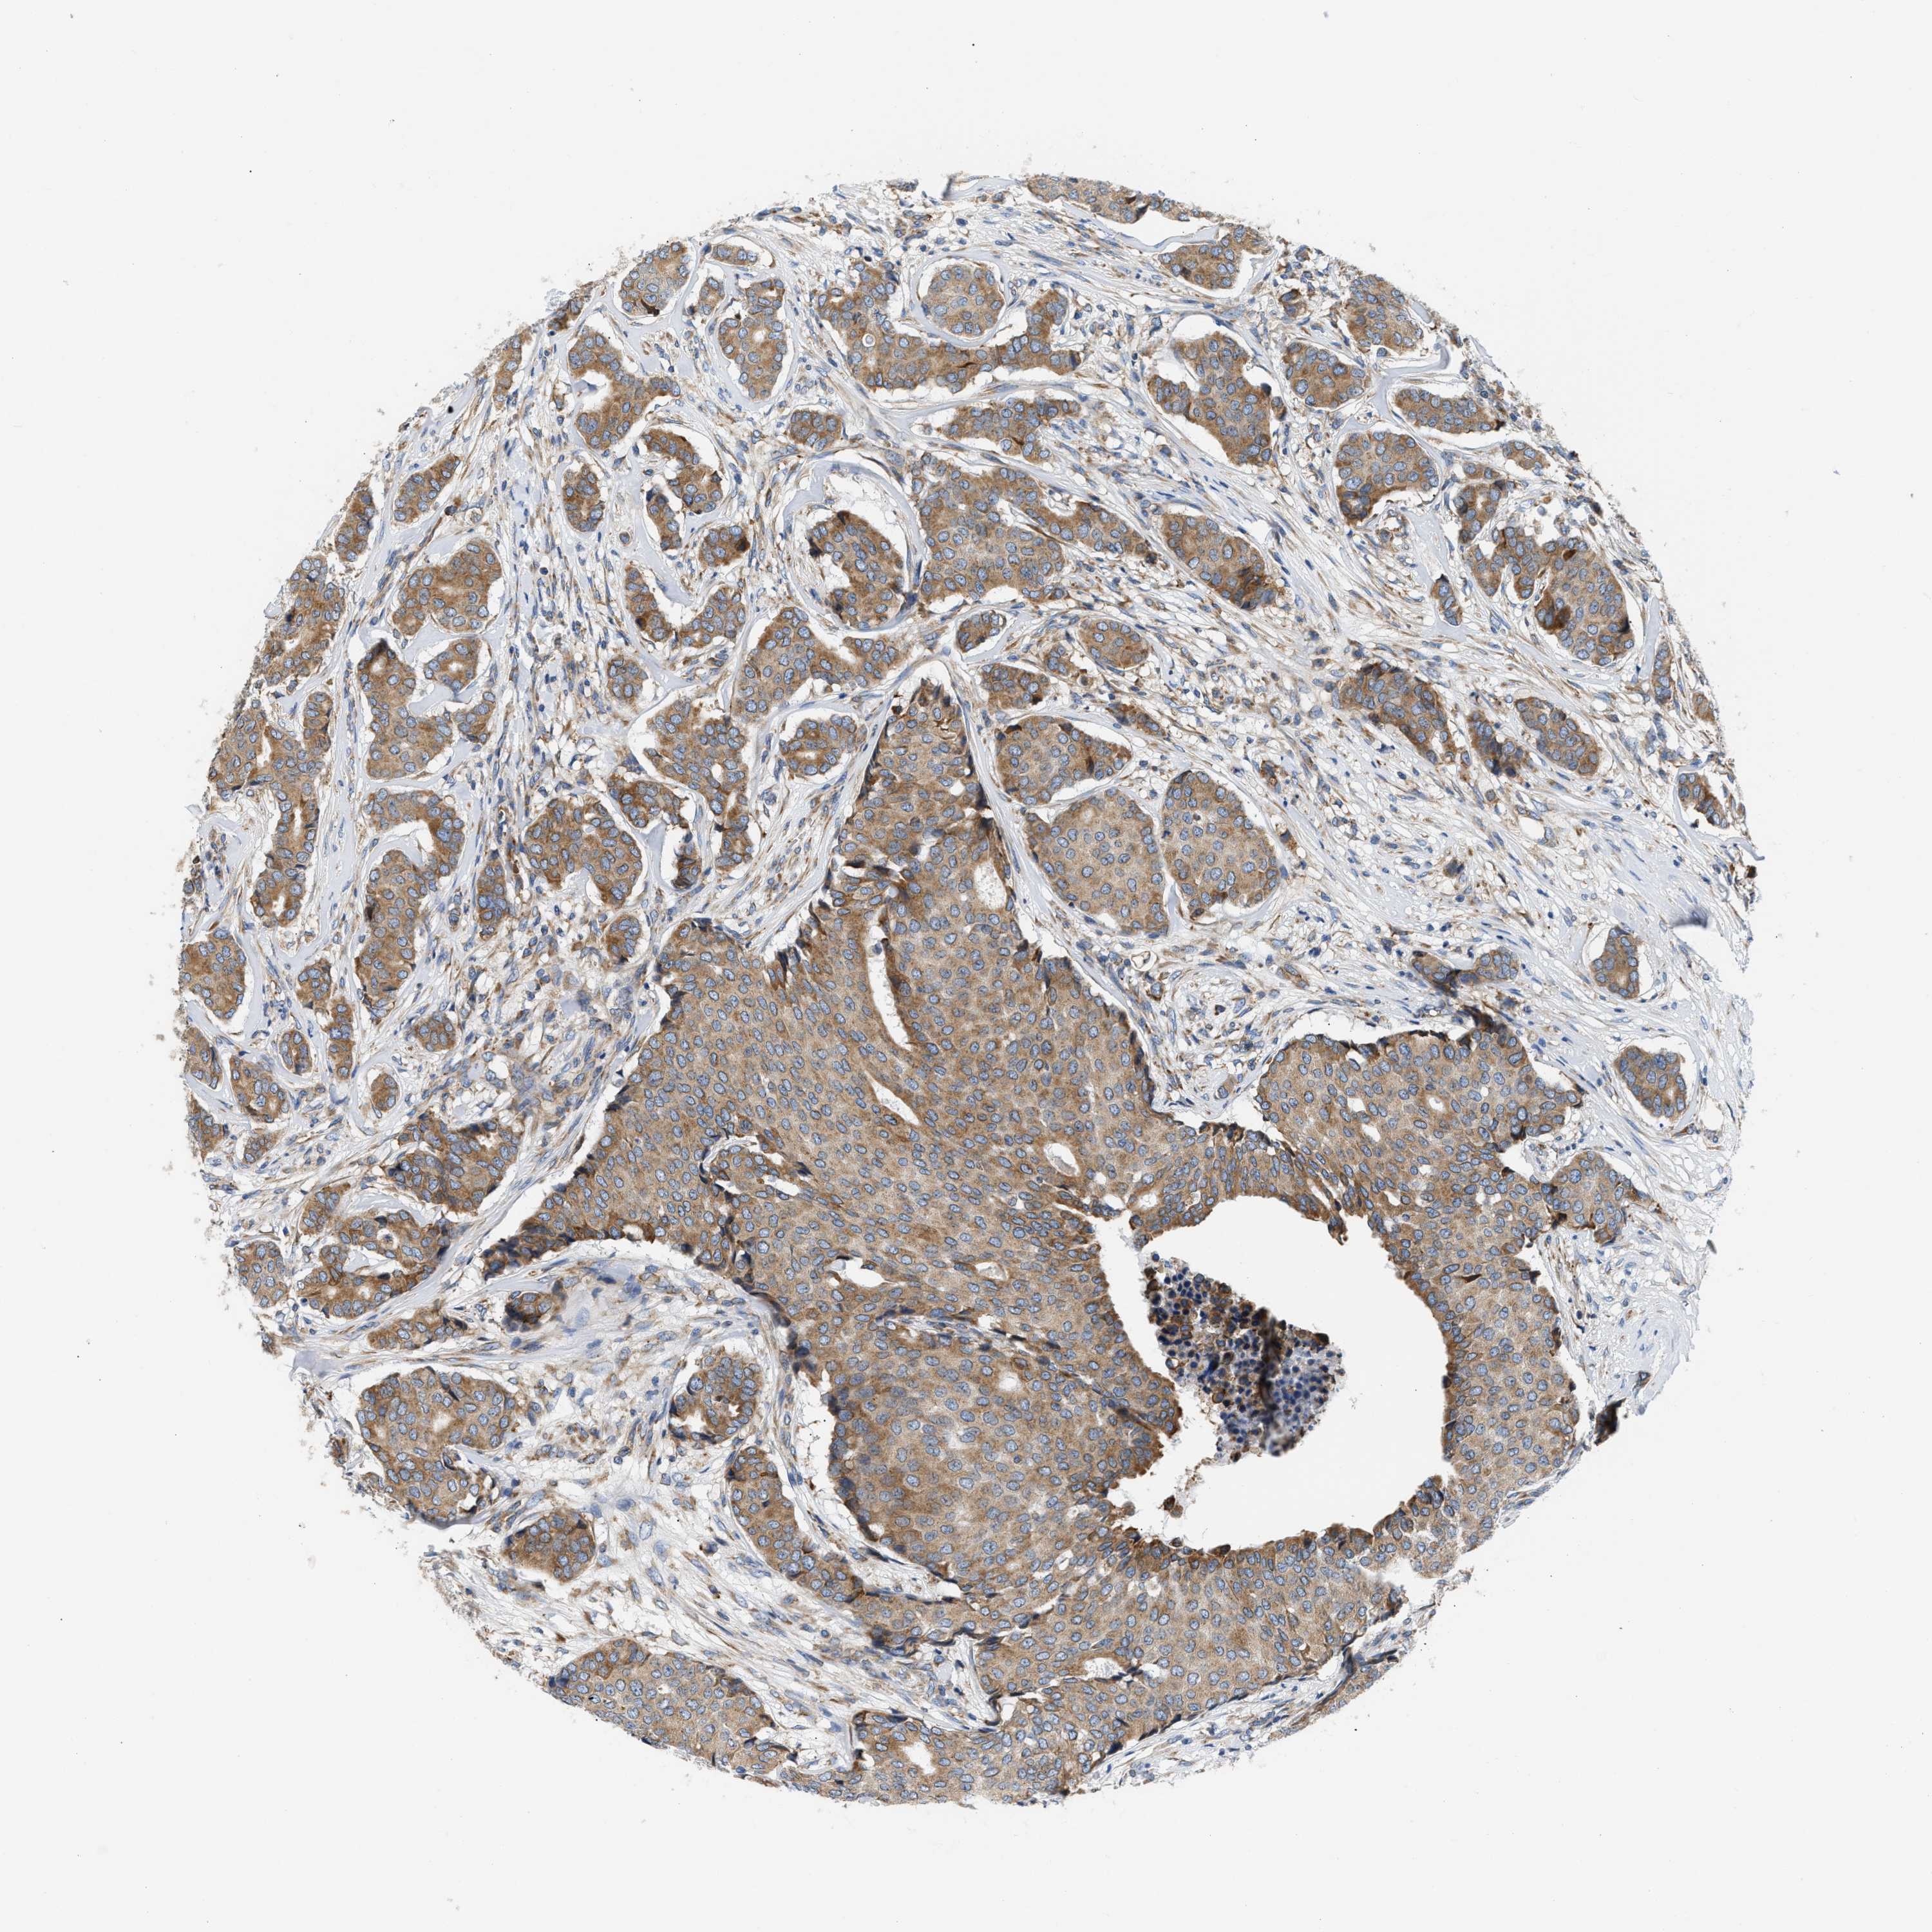

CANCER BREAST CANCER Show tissue menu

BRCA TCGA BRCA VALIDATION PROTEIN EXPRESSION

Breast cancer

Human cancer